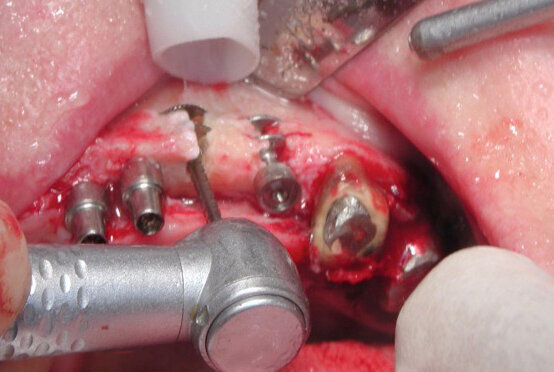

Pour cela, elle fait appel à des implants spécifiques (Diskimplant : (Fig 2a, b)) permettant un ancrage dans l’os basal de la face, non soumis à la résorption, ainsi qu’à des techniques issues de la chirurgie maxillo- faciale.

Fig. 8a : L’ostéotomie préalable à l’insertion de l’implant se réalise le plus souvent latéralement (Photo : EPSON)

Fig. 8b : L’ostéotomie préalable à l’insertion de l’implant se réalisant le plus souvent latéralement

Dans le cadre de cette nouvelle approche conceptuelle, l’étudiant va, devoir modifier sa vision traditionnelle de l’ancrage endo-osseux propre aux vis qu’il a l’habitude d’installer par voie crestale. L’ostéotomie préalable à l’insertion de l’implant se réalisant le plus souvent latéralement : (Fig 8a, b), il faudra en plus de l’évaluation des paramètres verticaux (hauteur, profondeur) tenir compte surtout des dimensions dans le sens horizontal (largeur de la crête, épaisseur des corticales osseuses). Il faudra également se familiariser avec ces implants spécialisés.